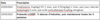

Des examens sanguins (tableau 1) sont réalisés, ainsi qu'une échographie abdominale (sans anomalie visible).